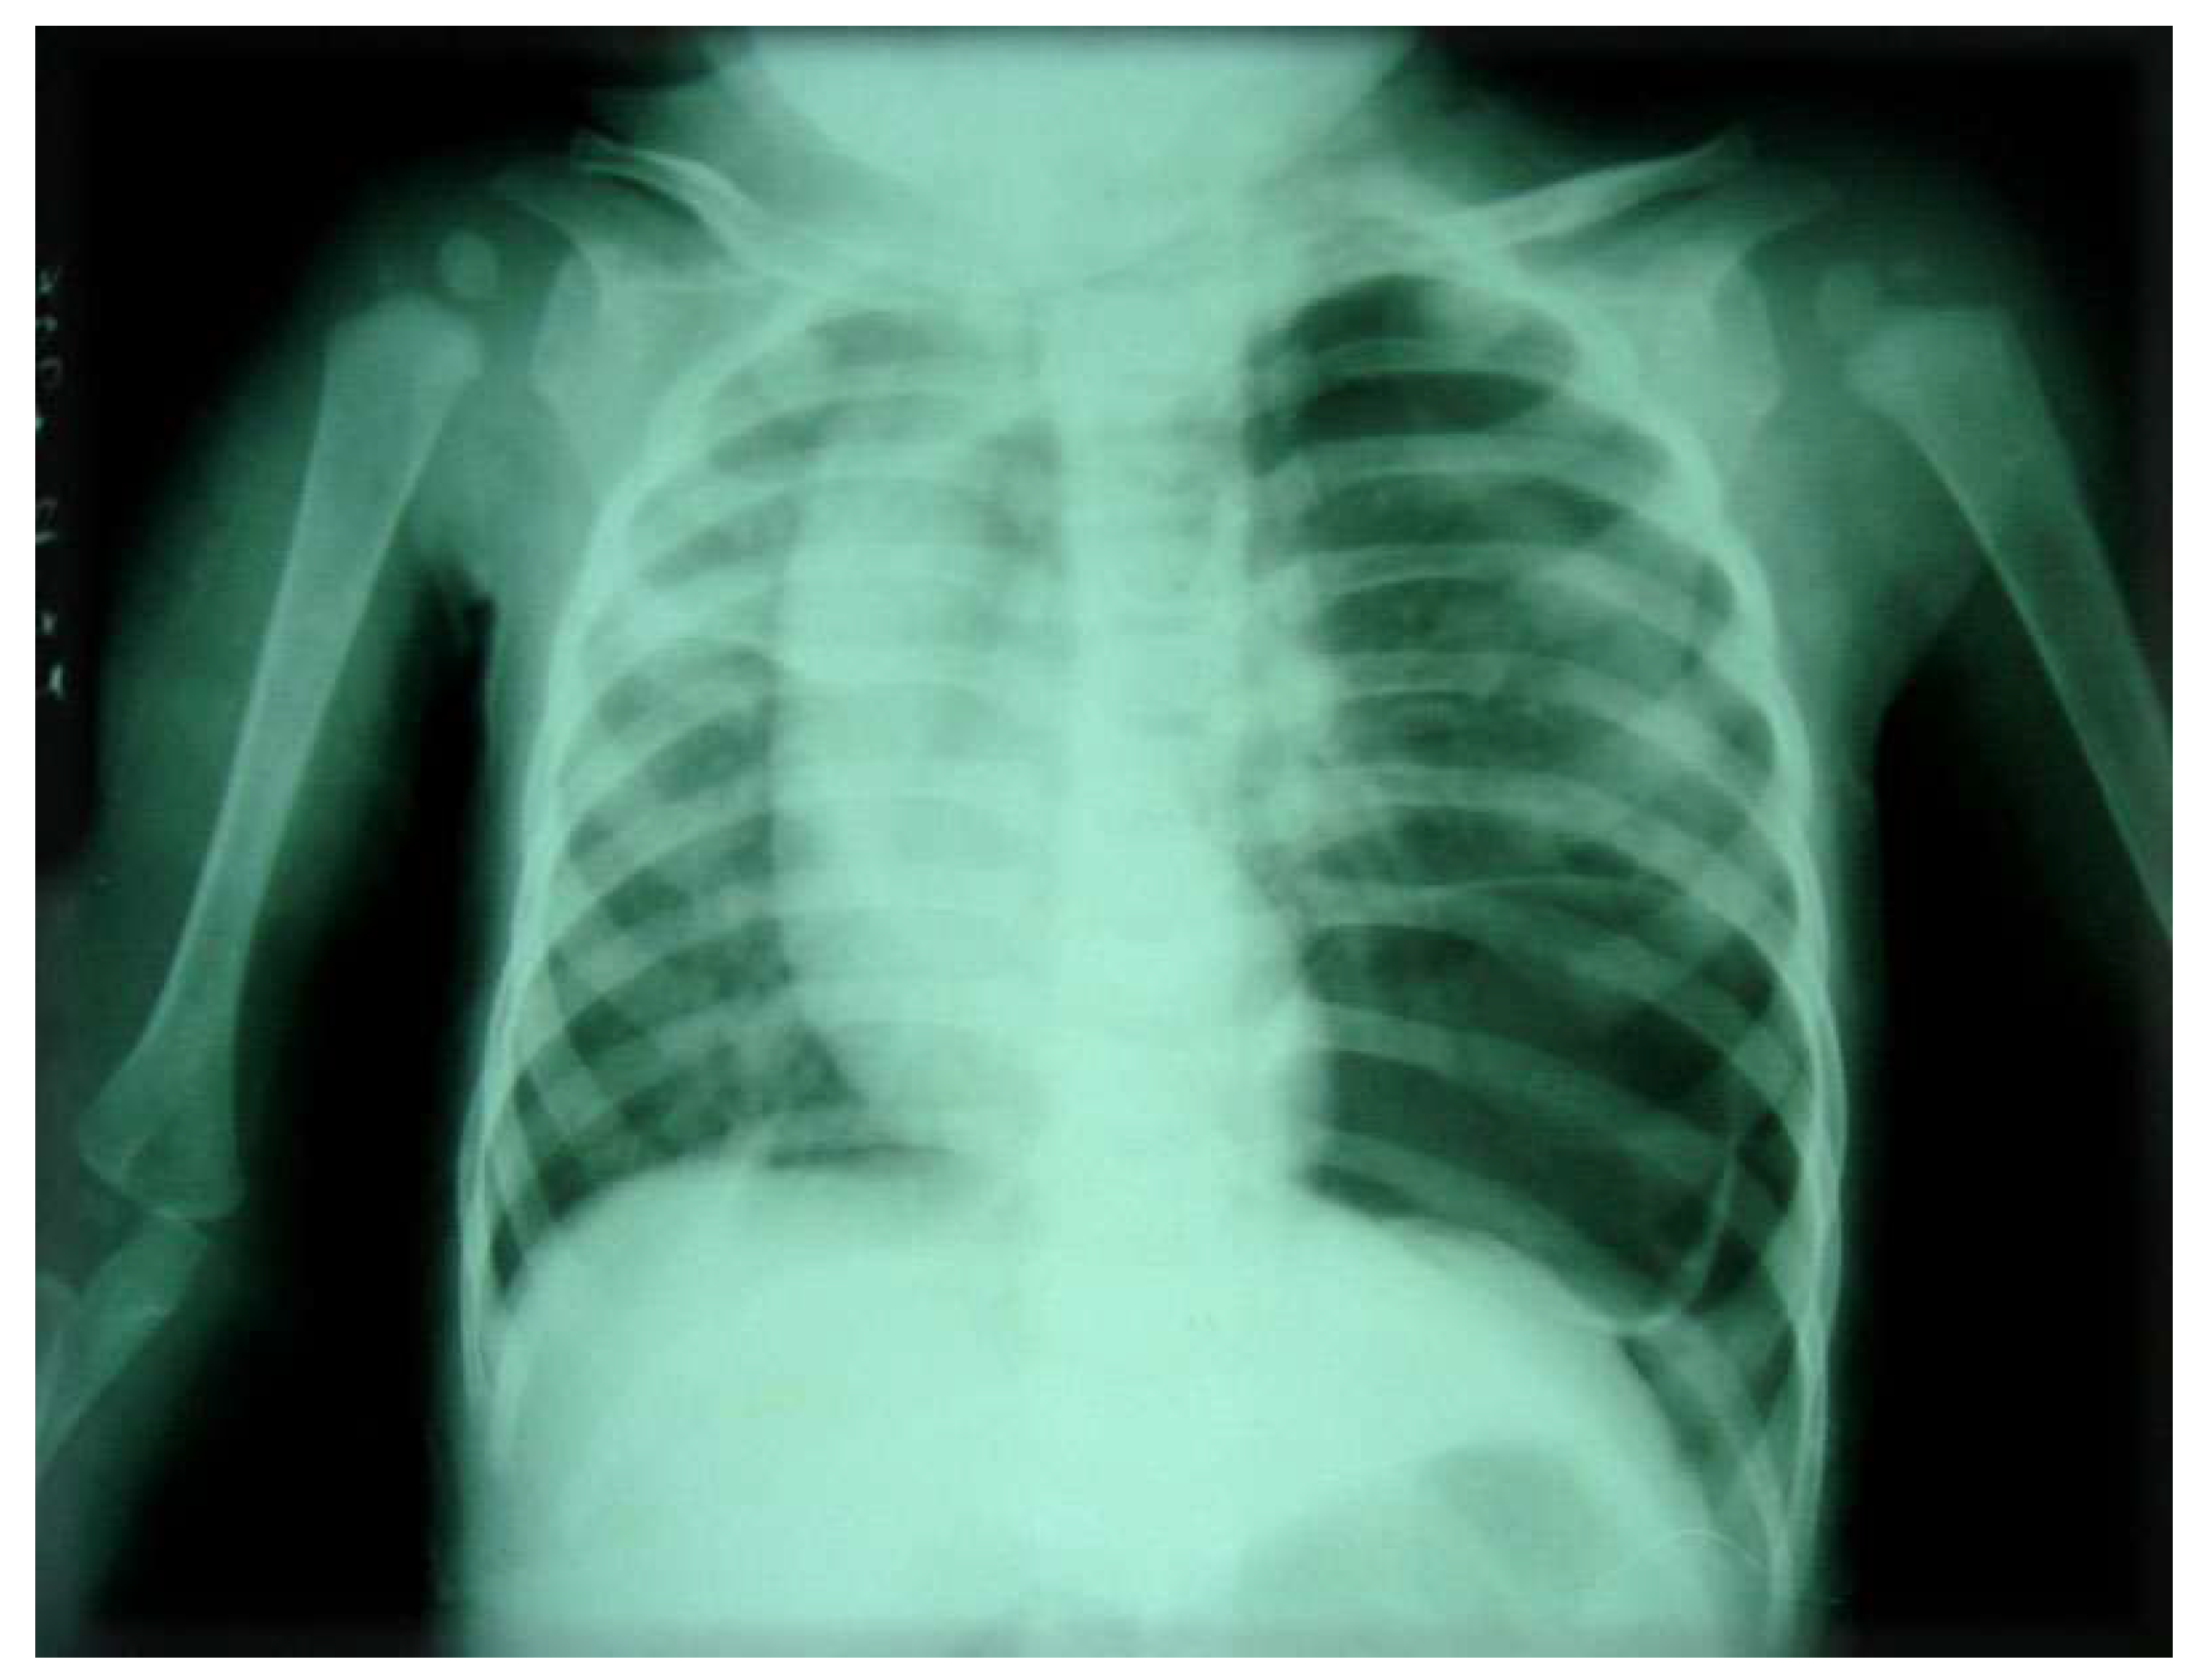

A nasogastric tube was placed, and an abdominal x-ray was obtained to confirm the diagnosis. A subsequent radiograph revealed the nasogastric tube advancing into the left thoracic cavity (Figure 2).

Figure 2.

Preprints 179744 g002